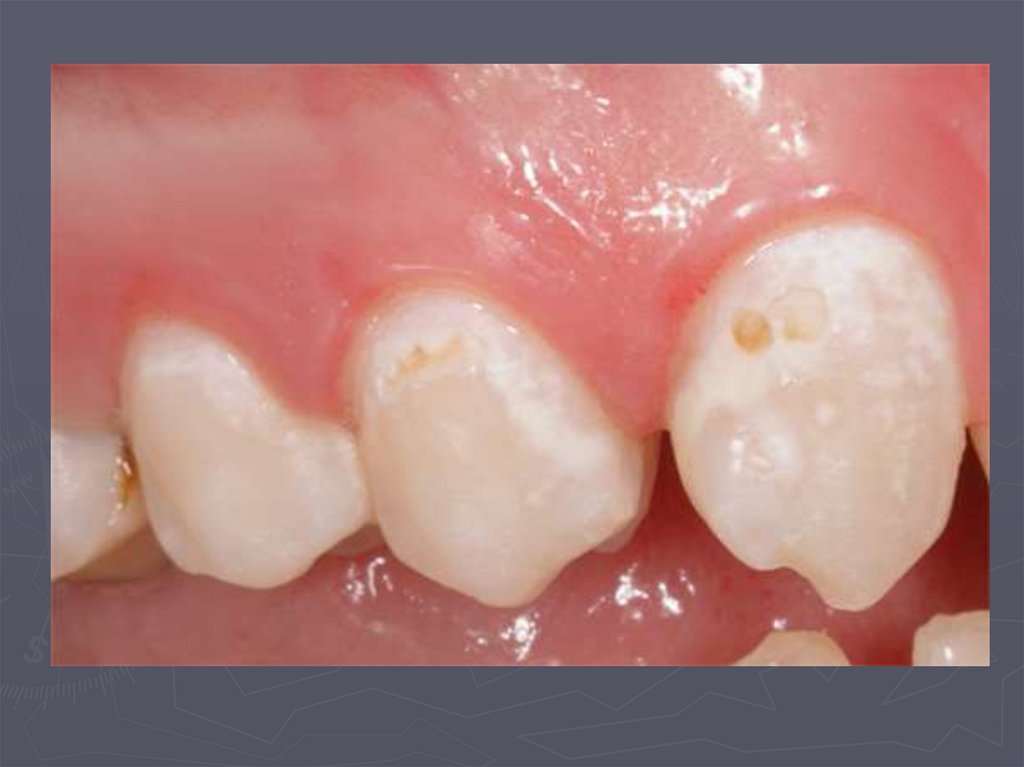

21. Начальный кариес (кариес в стадии пятна)

22. Начальный кариес (кариес в стадии пятна)

23. Начальный кариес (кариес в стадии пятна)

25. Начальный кариес (кариес в стадии пятна)

26. Начальный кариес (кариес в стадии пятна)

27. Начальный кариес (кариес в стадии пятна)